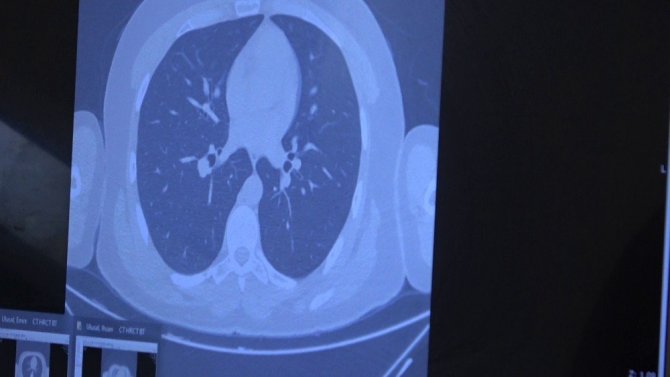

Korona geçirmiş bir ailenin akciğer tomografilerini inceleyen Prof. Dr. Özkaya, "Bir örnek vermek gerekirse, bu genç hastamız 26 yaşında, ailede ilk kez bu çocuk pozitif oluyor. Genç olduğu için hafif atlatıyor. Sonra annesini enfekte ediyor. Annesi çocuktan bir tık daha fazla akciğer tutulumuyla geliyor. Daha sonra da babası enfekte oluyor. Annesini tedavi ettik ama babası inanılmaz solunum yetmezliğiyle bize başvurdu. Yani virüs "akıllı bir organizma" gibi davranıyor. Ailede birini enfekte ettiği zaman diğer enfekte edeceği kişide bir tık daha kötü akciğer hasarı yapıyor. Bu konuda vatandaşlarımızın mutlaka aile içindeki temasa çok dikkat etmesi lazım. Virüs 2019'da bulundu, 2020'de salgın ilan edildi, hastalığın 2021'de daha kötü bir tabloya yol açmaması için herkesin dikkat etmesini ve aşı konusunda da duyarlı olmasını istiyoruz. Çünkü tek kurtuluşumuz şu an aşı gibi duruyor" şeklinde konuştu.